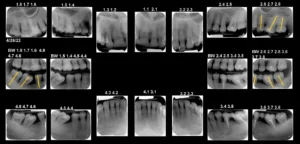

Dinții nu sunt fixați rigid în osul maxilar, ci sunt susținuți de ligamente periodontale elastice, care permit o ușoară mișcare. Atunci când un dinte este pierdut, dinții adiacenți pot migra pentru a ocupa spațiul gol, ceea ce poate duce la o mușcătură incorectă și la suprasolicitarea altor dinți. În timp, acest proces poate afecta întreaga structură a danturii și poate complica realizarea unor lucrări dentare stabile și funcționale.

Fără o aliniere corectă a dinților, lucrările dentare pot fi supuse unor forțe anormale, ceea ce poate duce la eșecul prematur al acestora. De exemplu, o coroană aplicată pe un dinte înclinat poate ceda, iar un implant poate fi compromis de o distribuție inegală a forțelor masticatorii. De asemenea, o mușcătură incorectă poate provoca tensiuni musculare și dureri articulare, afectând calitatea vieții pacientului.